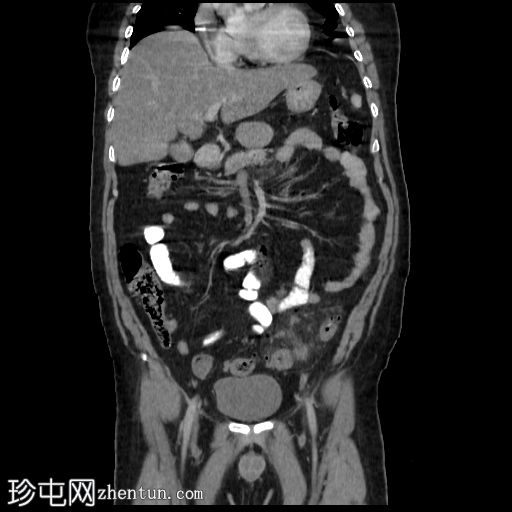

冠状位增强扫描(门静脉期)

降结肠和乙状结肠可见多个小憩室,伴有少量小(亚厘米级)区域淋巴结肿大。周围脂肪和肠壁无明显增厚。

远端降结肠后壁可见一小(<15 mm)、局限性空腔,内含气泡,伴有不规则肠壁强化和轻度邻近肠系膜脂肪条索状改变。

未见脓肿、腹水、弥漫性气腹,提示IA期复杂性急性穿孔性憩室炎(局部穿孔)。

轻度脂肪肝。